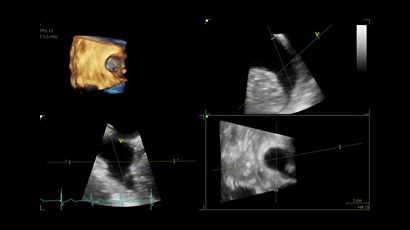

• Vivid IQ 4D с поддержкой технологии объемной реконструкции

• Передовые технологии, такие как 4D чреспищеводная эхокардиография, ЭКГ, стресс-эхо, внутрисердечная ультразвуковая эхокардиография, тканевый доплер и другие.

4D:

Да

• 4D AUTO AVQ - модуль автоматического выравнивания, сегментации и обсчета размеров кольца аортального клапана по объемным данным.

• 4D AUTO LVQ - модуль расчета массы миокарда ЛЖ на основе данных 4D-исследования.